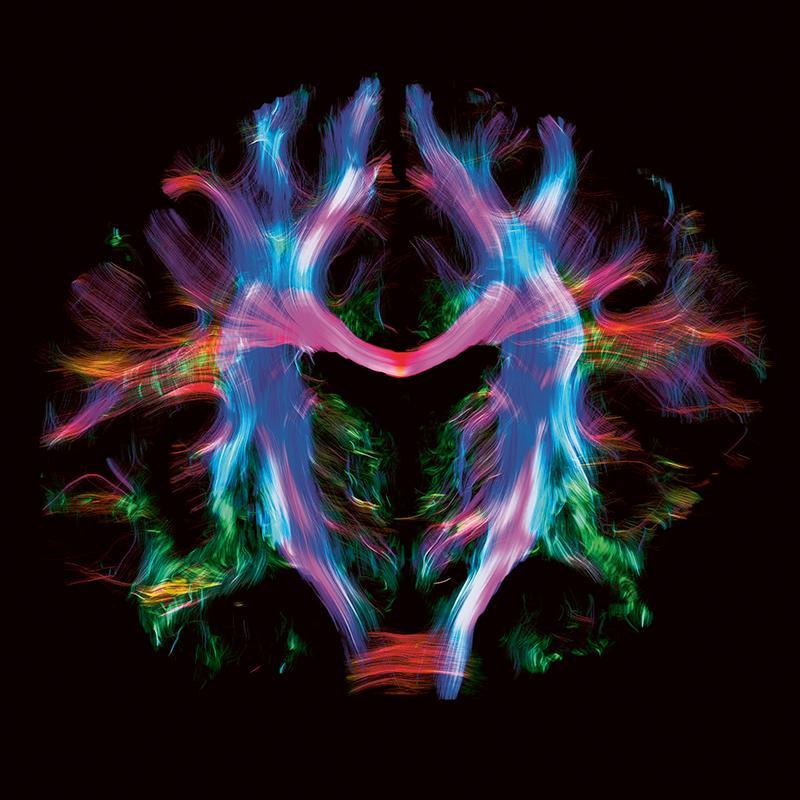

Grâce au fort signal de l'IRM 7T, il est possible de voir les fibres allant d’une région cérébrale à l’autre et se croisant dans certaines sub-régions cérébrales.

Image montrant différents composants du cerveau.